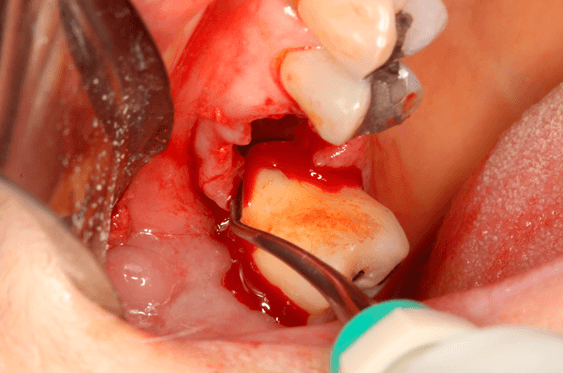

Avaliamos o desempenho do biomaterial de hidroxiapatita com colágeno tipo I (Extra Graft XG-13®) na manutenção do volume alveolar.

A aplicação como o caso clínico abaixo se mostrou uma técnica acessível a todos cirurgiões dentistas, pois se trata de um procedimento de simples execução e acessível. Logo, deveria constar na clínica diária.